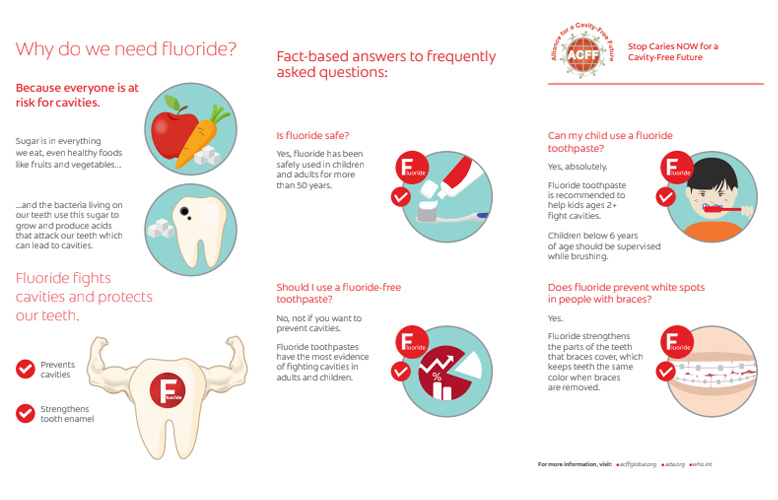

¿Qué es el flúor?

Es un mineral natural que se encuentra en la corteza terrestre y tiene una distribución extensa en la naturaleza. Algunos alimentos y depósitos de agua contienen fluoruro.

Adultos y flúor

¿Se pueden beneficiar los adultos del flúor? Nuevas investigaciones demuestran que todas las personas se pueden beneficiar del flúor. Los expertos pensaban que el flúor trabajaba principalmente fortaleciendo los dientes durante su desarrollo, lo que dio pié para que los niños fueran el foco de los esfuerzos de fluoración.

Cómo tener la conversación sobre el fluoruro

La conversación acerca de la aplicación de fluoruro nunca debería terminar. Es importante hablar con padres y madres acerca de los beneficios del fluoruro y de por qué con los cambios en los horarios y las rutinas el tema es más importante que nunca.

El fluoruro y su paciente: cómo iniciar la conversación

¿Podría serles útil a sus pacientes un tratamiento de fluoruro en casa o en el consultorio? A continuación, le decimos cómo puede iniciar una conversación como higienista dental acerca de los beneficios del fluoruro.

Fluoruro: nuestros 5 consejos sobre cómo informar a los padres y madres

Frente a la gran cantidad de desinformación que hay acerca del fluoruro y la fluorosis, ¿cómo pueden las y los profesionales de la salud dental hablar con madres y padres preocupados por los efectos del fluoruro en sus hijos e hijas?

Cómo responder a las preguntas de sus pacientes acerca del flúor

Cómo hablar con sus pacientes de manera efectiva acerca de los beneficios del flúor y de la desinformación que hay al respecto.